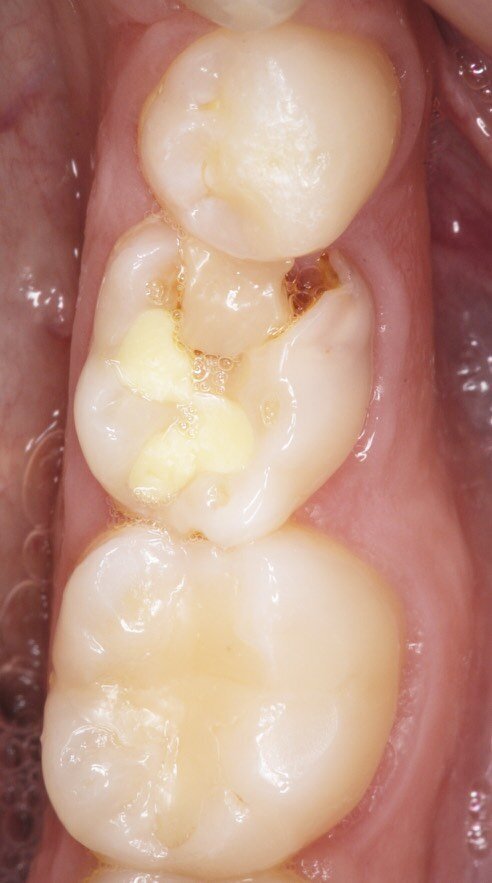

Fig. 2_Visualizzazione occlusale sx.

Fig. 3_Visualizzazione occlusale dx.